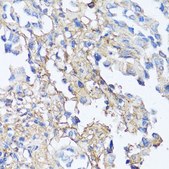

immunohistochemistry: 1:50-1:200

This gene encodes fibronectin, a glycoprotein present in a soluble dimeric form in plasma, and in a dimeric or multimeric form at the cell surface and in extracellular matrix. The encoded preproprotein is proteolytically processed to generate the mature protein. Fibronectin is involved in cell adhesion and migration processes including embryogenesis, wound healing, blood coagulation, host defense, and metastasis. The gene has three regions subject to alternative splicing, with the potential to produce 20 different transcript variants, at least one of which encodes an isoform that undergoes proteolytic processing. The full-length nature of some variants has not been determined.

Recombinant fusion protein containing a sequence corresponding to amino acids 2200-2355 of human Fibronectin (NP_002017.1).